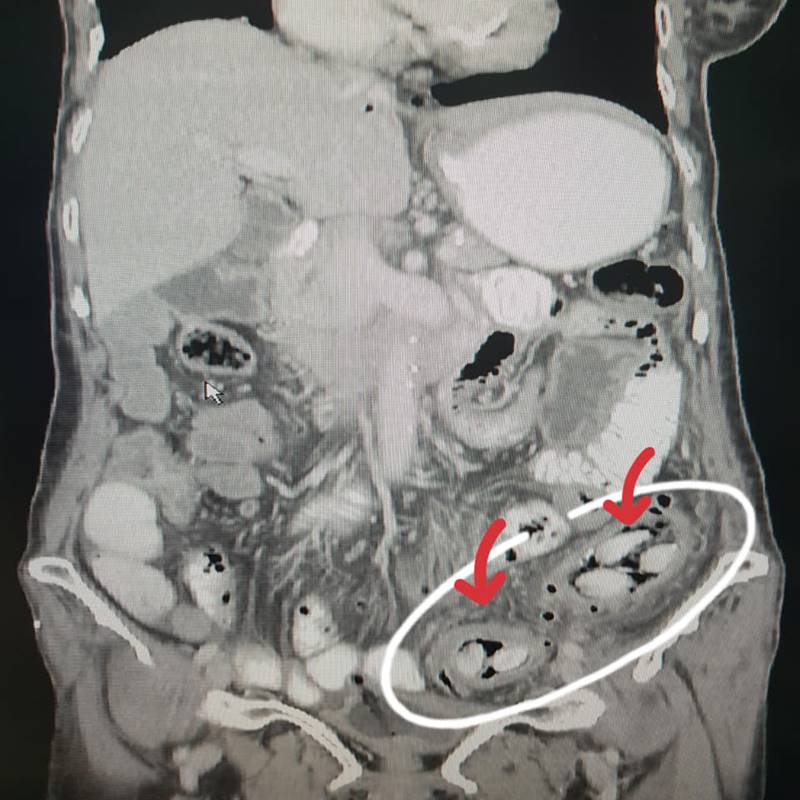

โดยระบุว่า โรคนี้เป็นปัญหาที่พบได้บ่อยในช่วงนี้เพราะกระท้อนออกผล โดยเฉพาะผู้สูงอายุที่ไม่มีฟัน เวลากินกระท้อนชอบดูดเม็ด ดูดเพลิน ๆ เม็ดหลุดลงคอได้ ถ้าเป็นเม็ดผลไม้อื่นคงไม่มีปัญหา แต่เม็ดกระท้อนเจ้ากรรม มีลักษณะเรียว หัวแหลมท้ายแหลม ชอบไปกองในลำไส้และทิ่มลำไส้จนแตกทะลุ

ภาพจาก เฟซบุ๊ก Jirat Jiratham-opas

คนไข้มาถึงโรงพยาบาลส่วนใหญ่ อาการมักรุนแรง เนื่องจากอุจจาระแตกเต็มท้อง บางรายความดันโลหิตตก ต้องให้ยากระตุ้น บางรายถึงขั้นเสียชีวิต ส่วนคนไข้ที่ต้องผ่าตัดจะมีแผลยาวกลางท้อง โดยต้องตัดไส้ที่แตกออก ล้างอุจจาระในท้องและต้องยกทวารเทียม แผลผ่าตัดไม่สามารถเย็บปิดได้เพราะมีโอกาสติดเชื้อสูง ต้องทำแผลทุกวัน เช้า-เย็น ทรมานอีกเป็นสัปดาห์กว่าจะเย็บปิดได้